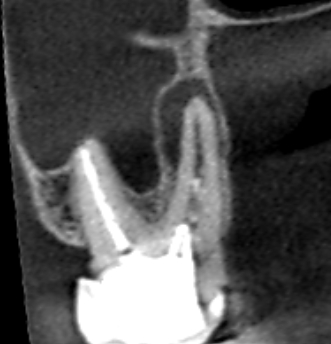

初診時の上顎第二大臼歯の冠状断のCT画像です。

赤い矢印の先の口蓋根の横に長い膿の影がみられます。歯根破折や根尖孔外感染が疑われるケースです。